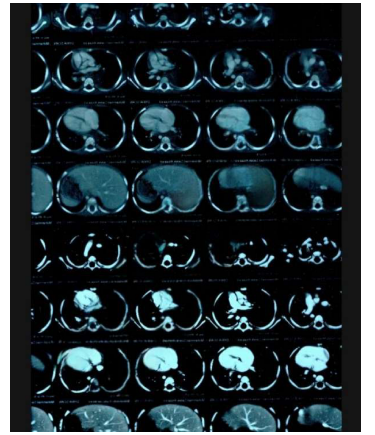

A contrast-enhanced Computer Tomography Scan of the chest showed: a large mass filling the posterior mediastinum in it's upper and middle parts, aligned with the visceral side of the right upper lobe.

MRI showed: a mass in the posterior mediastinum surrounding the tracheal branch and reaches the diaphragm, surrounding the Azygos vein, superior vena cava, aorta, major vessels and esophagus, measuring (11*5*7) cm. and foci osteolysis in the 9,11,12 thoracic vertebrae.